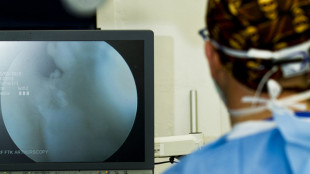

Tumori della cervice, una tecnica innovativa per la diagnosi precoce

Si basa sull'utilizzo della spettroscopia Raman che analizza le molecole dei tessuti